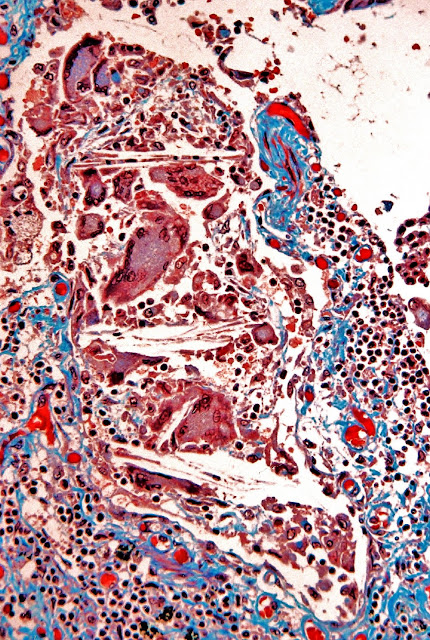

FIG.-14.-La respuesta tisular a la presencia de cristales de colesterol.

Pulmón perteneciente a otro caso.

Granuloma de colesterol en el que se observan numerosísimas células gigantes multinucleadas además de macrófagos y linfocitos.

Tricrómico de Masson.